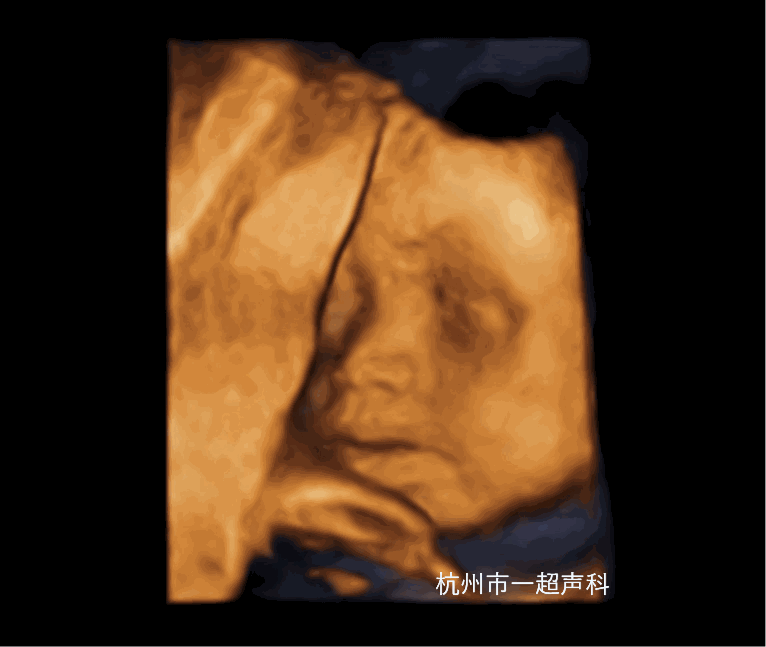

产前超声诊断

我院在2009年开展超声产前诊断,为杭州市第一家取得产前诊断资质的医疗机构,技术实力雄厚,超声产前诊断学组目前有主任医师2名,副主任医师3名,高级职称占62.5%,并在市内较早开展了胎儿超声心动图、早中孕期胎儿筛查,超声引导下羊水、绒毛、脐血穿刺、选择性减胎术、宫内输血术等。